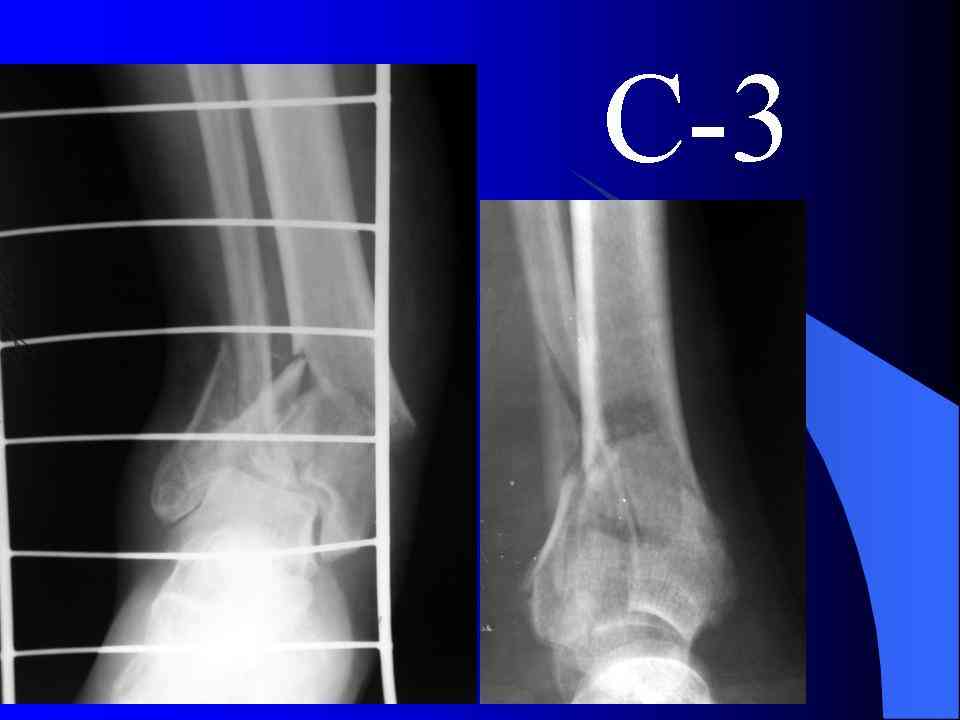

На рентгенограммах типичный перелом пилона по типу С-3. есть опыт до 100 открытых опреаций у нас в клинике. 20 примерно в год. Принцип один -все внутрисуставные переломы нуждаются в открытой репозиции и внутренней стабильной фиксации. При поступлении КТ не надо, так как получается только нагромождение костей. Истинной картины нет. Главное восстановить длину малоберцовой кости - это ключ к успеху. При поступлении меньше всего надо думать о сосудистых расстройствах, т.к. сама операция и репозиция даже сначала частичная даёт улучшение сосудитых нарушений. Причём очень быстро. Операция в 2этапа. При поступлении доступ позади наружной лодыжки, причём обязательно. После этого репозиция малоберцовой кости и фиксация пластиной 1/3 трубки под винт 3,5. Дренаж и любой аппарат наружной фиксации. Затем после спадения отёка на 5-7-10 день аппрат снимается и дугообразный разрез спереди от медиальной лодыжки 10-12 см. Главной чтобы расстояние между 1 и вторым разрезом было не меньше 7-8 см. Тогда не будет некрозов лоскутов. Таранная кость используется как матрица на неё укладываются отломки и фиксируются пицами. Ренг-контроль. Отломки лежат все отдельно, но ничего не высыпется. При переломах С-3 всегда нужна костная пластика (из крыла). Фиксация пластиной лист клевера простой или LCP. Гипс не нужен. Дренаж до 48 часов. Операция длится 3-4 часа обязательно без жгута. Посылаю примерно такой же случай.